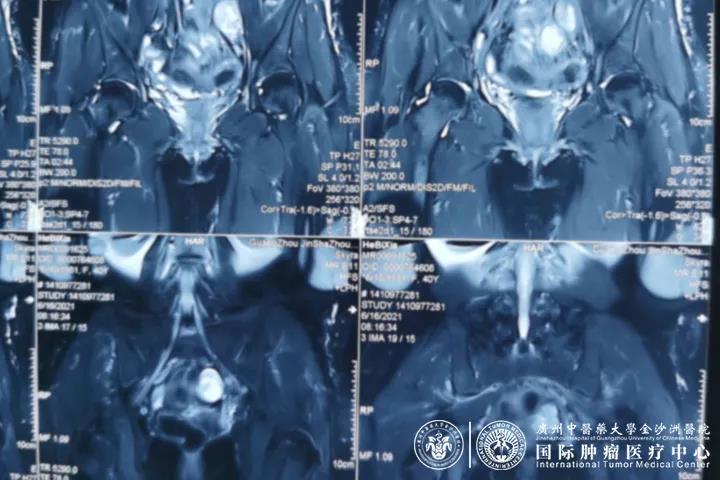

经过一系列的系统治疗后,何女士的病情日趋好转。何女士的全腹部+盆腔MR复查报告显示,子宫内膜癌综合治疗后,病灶较前明显缩小。目前,何女士的病情一天比一天好起来,恢复良好。